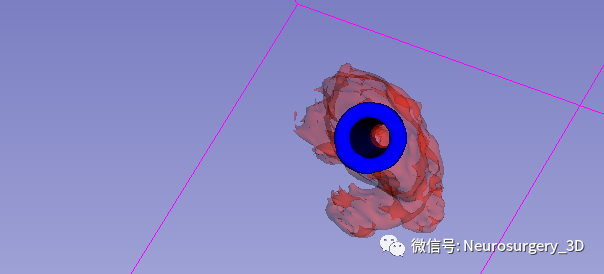

2、建立穿刺导管

3、生成空管

4、生成穿刺导板面具